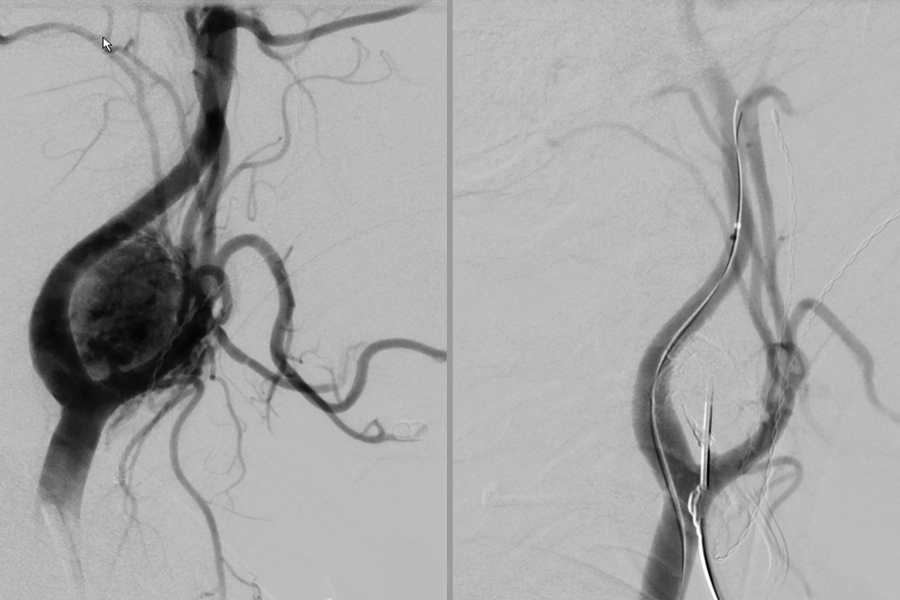

- Verschluss von Aneurysmen der Hirnschlagadern (z.B. mit Coils, Flow-Divertern, Ballon- oder Stent gestützen Vefahren)

- Embolisation von angeborenen und erworbenen Gefäßfehlbildungen des zentralen Nervensystems wie Arterio-Venösen Malformationen (AVM) oder duralen Fisteln